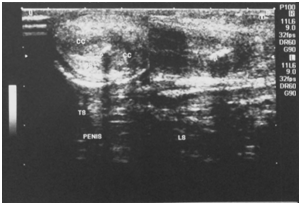

A 48year old male patient , a known diabetic presented with a palpable hard nodular lesion in the middle third of penis since 6months. Local USG of penis showed linear echoreflective calcified plaque in intercorporeal septum extending along the ventral aspect of bilateral corpora cavernosa causing posterior acoustic shadowing (Figure 1A & Figure 1B). A diagnosis of Peyronie’s disease was made. Plain radiograph of penis done with soft tissue exposure confirmed calcification (Figure 2).

Figure 1A Ultrasound mid penile shaft tranverse section shows echoreflective calcified plaques in intercorporeal septum with extension along ventral aspect of bilateral corpus cavernosa (right >left).

Figure 1B Ultrasound penile shaft longitudinal section showing multiple echoreflective calcified plaques in intercorporeal septum with extension along ventral aspect of bilateral corpus cavernosa.